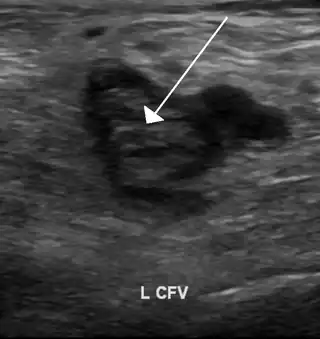

Una imagen de ultrasonido que muestra un coágulo de sangre en la vena femoral común izquierda. | ||

La mayoría de las personas que tienen una trombofilia no presentan síntomas. No obstante, algunas desarrollan un coágulo de sangre, o trombosis. Con frecuencia, los coágulos sanguíneos se forman en las venas de la parte inferior de la pierna y producen hinchazón, enrojecimiento y malestar. Este trastorno, llamado trombosis venosa profunda, suele diagnosticarse mediante métodos de diagnóstico por imágenes que emplean ultrasonidos. Los coágulos suelen tratarse con medicamentos anticoagulantes.